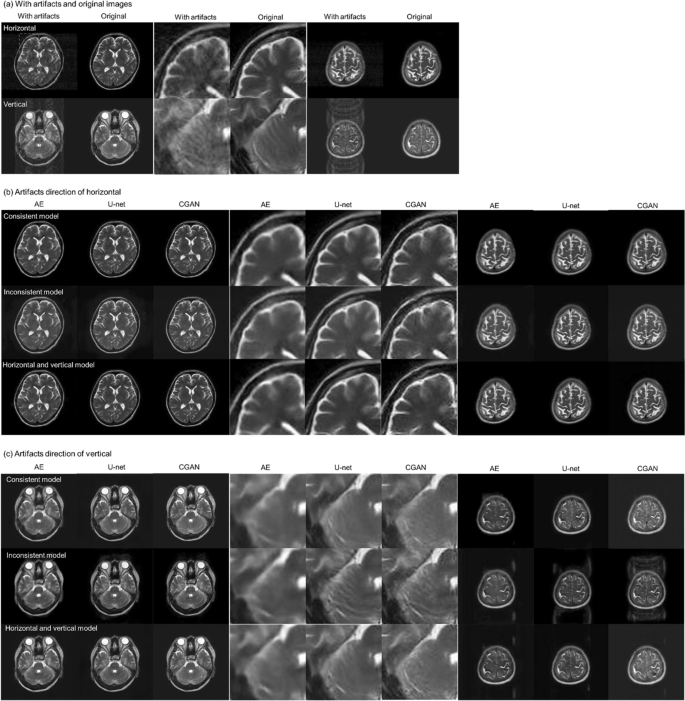

Figure 3 shows the results of motion artefact reduction using each deep-learning method in the AE, U-net, and CGAN models: (a) shows an axial slice image of two cases with motion artefacts in the horizontal and vertical directions, with the corresponding original MR images. (b) shows the results of the artefact reduction in the horizontal direction, and (c) shows the results in the vertical direction. For each result, there were three learning models: a consistent condition of directions in the motion artefacts with the verification image and training data, results of the inconsistent condition, and results of the training models using motion artefacts in both the horizontal and vertical directions. In each image, enlarged images of the region of interest (indicated in red in [a]) are shown at the center, and an example slice of the parietal image is shown on the right side. The simulated motion artefact images had a lower quality than the original MR images. These motion artefacts were reduced by image correction using each deep-learning method. However, the image resolution decreased significantly, and blurry images were generated using the AE model. In contrast, we observed that the U-net and CGAN models reduced motion artefacts while maintaining the image resolution. These models can effectively correct the image quality and visuality. Moreover, under conditions where the training data and motion artefacts of the images were not in consistent directions, the images of the motion artefacts remained near the eyeball, and the correction accuracy was insufficient. In the results of the parietal image, residual motion artefacts remained, and the pixel value consistency with the original image was degraded outside the head region. Tables 1 and 2 present the results of the comprehensive image evaluation using the structural image similarity (SSIM) and peak signal-to-noise ratio (PSNR). These results were presented as mean values and standard deviations for the evaluation of the 550 images synthesized using each deep-learning method. In the results of CGAN model, the SSIM mean was 0.925 ± 0.027, and the PSNR mean was 29.46 ± 2.37 dB, in the consistent condition. Therefore, the SSIM and PSNR values in the CGAN model significantly improved under conditions consistent with the direction of the motion artefacts in the training data. In contrast, the SSIM reached approximately 0.9, and the PSNR exceeded 29 dB in the CGAN model with the motion artefact model in both directions. Figures 4 and 5 show a comparison of the SSIM and PSNR values between the deep-learning models and the corresponding motion artefact images. These results were calculated under training conditions consistent with both the horizontal and vertical motion artefacts. After motion correction of the images using the CGAN method, the SSIM and PSNR significantly improved among the three deep-learning methods. Moreover, compared with simulated motion artefact images, the results of SSIM significantly improved by applying each deep-learning correction method; in contrast, PSNRs decreased in the result of the AE model.

Results of motion-corrected images by the autoencoder (AE), U-net, and conditional generative adversarial network (CGAN) models. (a) Simulated motion artefacts images and original magnetic resonance images, (b) Motion artefacts occurred in the horizontal direction, and (c) in the vertical direction. These models were trained using the image data; consistent with the direction of the motion, inconsistent with the direction of the motion, and with motion artefacts in the horizontal and vertical directions. Enlarged images of the region of interest, indicated in red a, are shown at the center of each image. For example, slices of the parietal image were shown on the right side of each image.